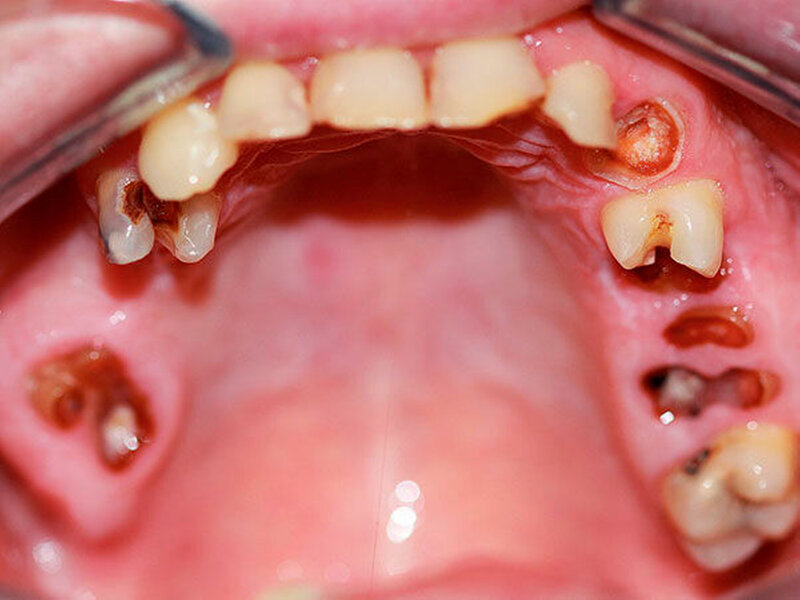

Bei chronischem Crystal-Meth(CM)-Konsum wurde eine Vielzahl körperlicher und psychischer Langzeitwirkungen, beispielsweise Herz-Kreislauf-Erkrankungen, strukturelle Hirnschädigungen und Persönlichkeitsveränderungen, beobachtet [Hamamoto et al., 2009]. In der aktuellen Literatur werden außerdem schwerwiegende Auswirkungen auf die Zahn-, Mund- und Kieferregion beschrieben [Hamamoto et al., 2009; Rhodus et al., 2008]. In den USA, wo nach Schätzungen knapp ein Drittel der weltweit über 30 Millionen CM-Abhängigen lebt, wurde 2005 erstmals der Begriff des „Meth mouth“ in der Fachliteratur genannt [Hamamoto et al., 2009; Rhodus et al., 2005] (Abbildung 1). Dabei wurden fünf Kardinalsymptome beschrieben: 1. Grassierende Karies (Abbildungen 2 und 3), 2. Gingivitis und Parodontitis, 3. Xerostomie, 4. Bruximus und 5. Trismus [Hamamoto et al., 2009; Rhodus et al., 2008].

Die Ergebnisse zeigen eine signifikant höhere Karies-, Gingivitis- und Parodontitisprävalenz innerhalb der Gruppe mit CM-Konsum als bei einer gleichaltrigen und vom Geschlecht gleich gewichteten Kontrollgruppe ohne CM-Konsum. Auffällig waren insbesondere eine signifikant verminderte Speichelflussrate und eine verminderte Speichelpufferkapazität bei der CM-Gruppe. Ein CM-induzierter Trismus durch den Nachweis einer eingeschränkten Mundöffnung war nicht ersichtlich. Signifikant erhöhte Schlifffacetten weisen auf einen durch chronischen CM-Konsum hervorgerufenen Bruxismus hin. Ebenso ist bei der CM-Gruppe eine verminderte Mundhygiene zu beobachten Tabelle 1).